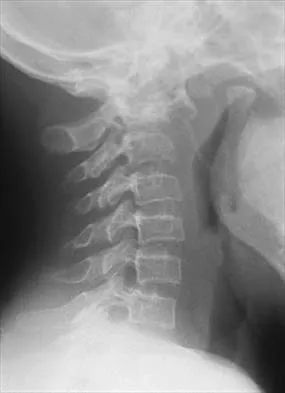

Figure 16 shows the radiograph of a 56-year-old man who has neck pain after a rollover accident on his lawnmower. The injury appears to be isolated, and he is neurologically intact. Management of the fracture should consist of